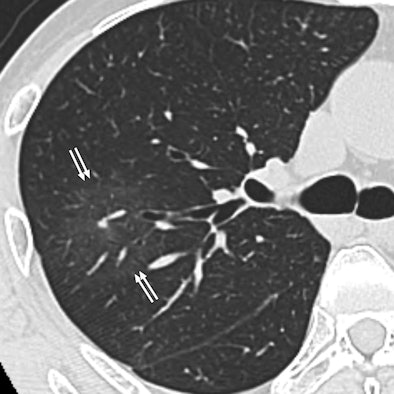

| 60-year-old man with metastatic squamous cell carcinoma from oral cavity. Above, axial CT scan obtained before tomotherapy shows mass (arrow) in left lower lobe, target lesion. Below, one-month follow-up CT scan shows focal ground-glass opacity (arrows) at periphery of target, representing radiation pneumonitis. |